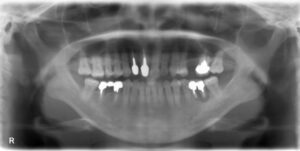

• 下顎オールオン6症例

BEFORE AFTER 78歳女性/下顎6本 【治療内容】 下の歯が、骨吸収により全体的に揺れている状態で来院された患…